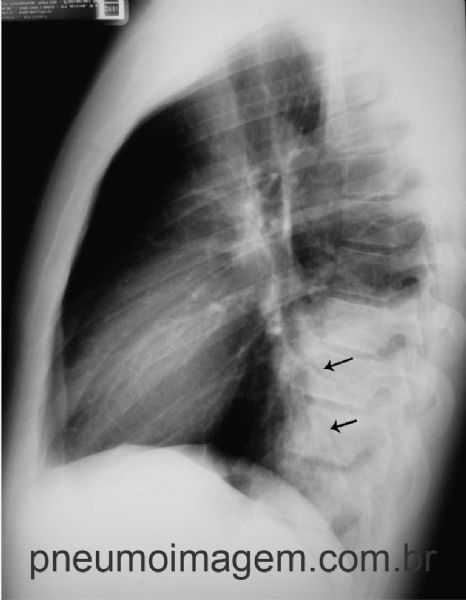

A incidência em perfil caracteriza bem a localização no lobo inferior. Observe que a sombra cardíaca encontra-se normal. Há a presença de broncogramas aéreos no interior da opacidade (seta).